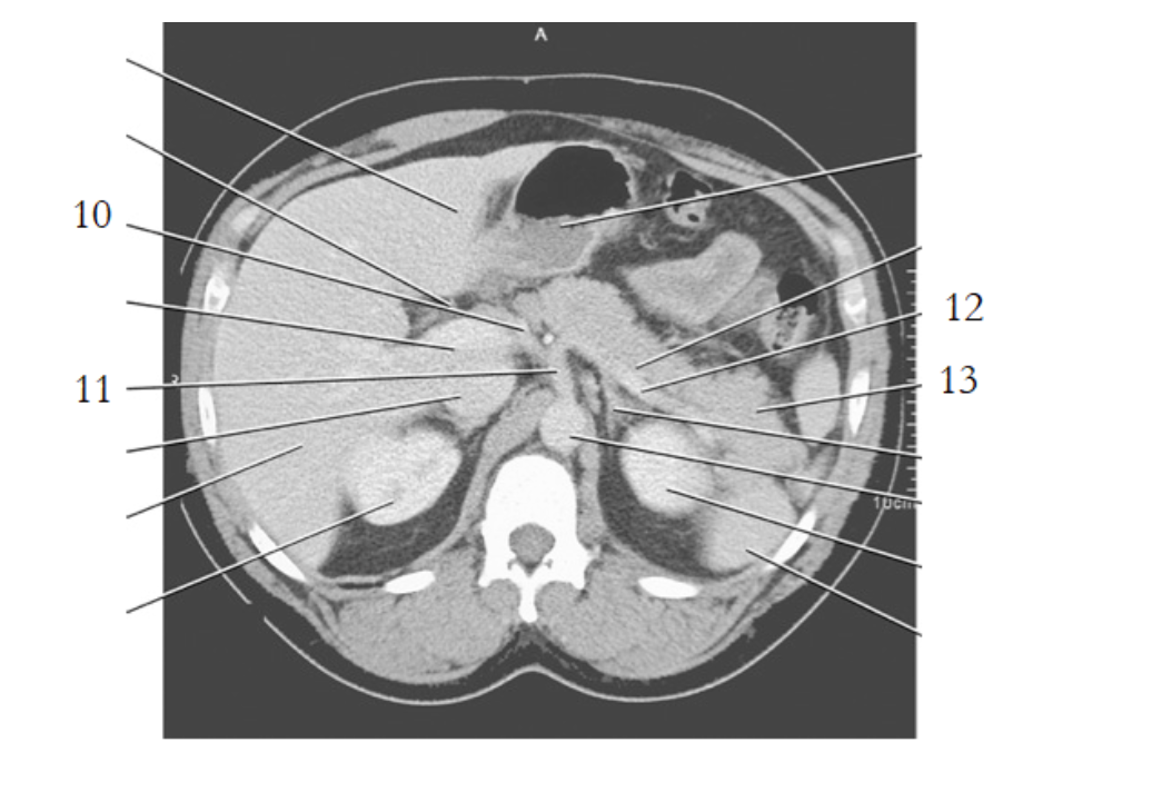

celiac axis

splenic artery

portal vein

aorta

left renal vein

pancreas tail

kidney

small bowel

large bowel